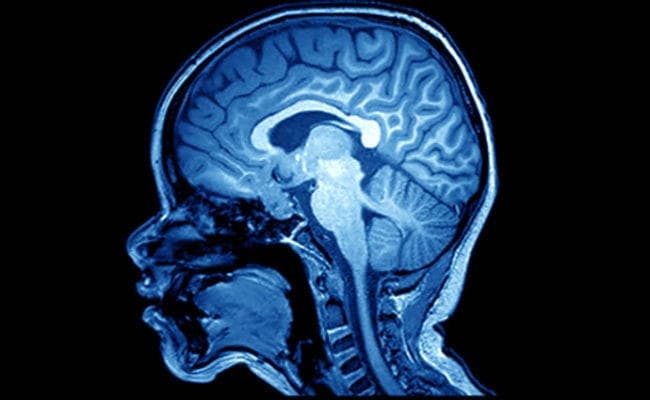

वाशिंगटन : वैज्ञानिकों का कहना है कि मस्तिष्क का ऐसा स्कैन जो यह दिखाता है कि मस्तिष्क के क्षेत्र किस प्रकार परस्पर प्रभाव डालते हैं इससे माइग्रेन , तनाव , बायपोलर विकार सहित मस्तिष्क से संबंधित कई अन्य बीमारियों का पता लगाने में मदद मिल सकती है.

‘न्यूरॉन’ जर्नल में प्रकाशित एक अध्ययन के अनुसार फंक्शनल कनेक्टिविट एमआरआई ( एफसीएमआरआई ) नाम का स्कैन किसी व्यक्ति का मस्तिष्क किस प्रकार से बंधा है इसमें आसानी से मूल अंतर का पता लगाने में सक्षम है. यह एमआरआई विश्वसनीय है.

स्वस्थ व्यक्ति और मस्तिष्क की बीमारियों से ग्रसित व्यक्ति के बीच अंतर पता करने की क्षमता भी इस तकनीक के पास है. वाशिंगटन यूनिवर्सिटी स्कूल ऑफ मेडिसिन की प्रोफेसर स्टीवन पीटरसेन ने बताया , ‘ यह फंक्शनल क्नेक्टिविटी एमआरआई के महत्व बताने की तरफ बढ़ाया गया कदम है.’

पीटरसेन ने बताया , “इससे पहले कि हम एफसीएमआरआई के आधार पर बीमारी का इलाज शुरू करें , हमे यह पता होना चाहिए कि यह वास्तव में क्या माप रहा है. हम यहां दिखाते हैं कि यह वह नहीं माप रहा है जो आप सोच रहे हैं बल्कि यह इस बात की माप कर रहा है कि आपका मस्तिष्क कैसे बना हुआ है. इस बात ने क्लिनिकल जांच के नए दरवाजे खोल दिए हैं.”